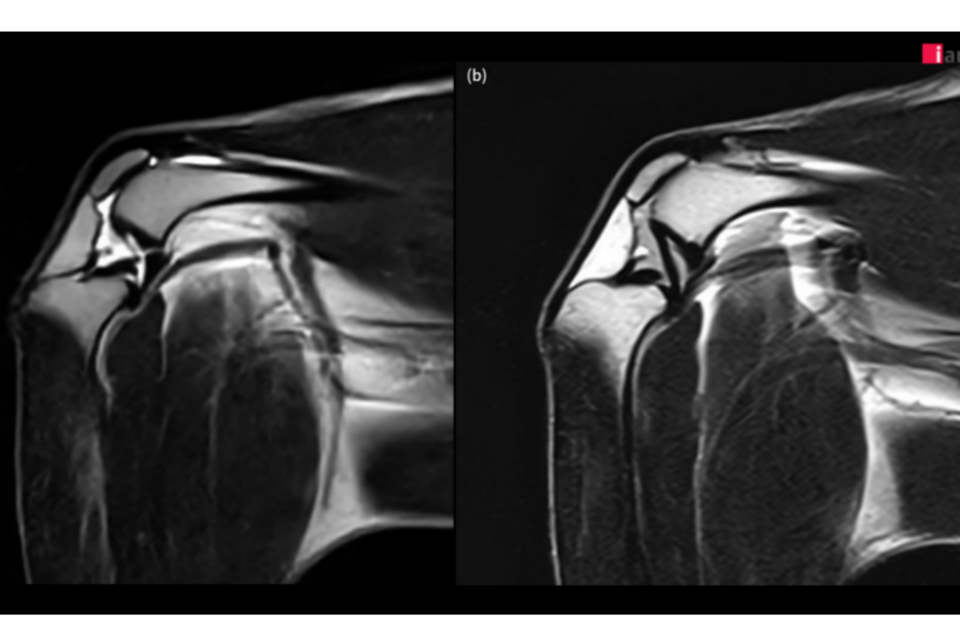

2023년 말부터 본격 가동된 이안동물의학센터의 AI 기반 MRI 소프트웨어는 딥러닝 알고리즘을 활용해 노이즈를 효과적으로 제거하고, 이미지 선명도를 대폭 향상시켰다. 특히 무릎 관절처럼 작은 구조물들이 복잡하게 얽혀 있는 부위에서 기존 영상 기법으로는 명확하게 파악하기 어려웠던 인대, 연골, 활액낭 및 인접한 근육 등의 세부 구조물까지 뚜렷하게 확인할 수 있어 정밀 진단에 큰 도움이 되고 있다.

이안동물의학센터는 정형외과에서 무릎 질환은 MRI로 진단하기에 가장 까다로운 분야 중 하나라며, AI 기술을 통해 MRI의 화질이 개선됨에 따라 십자 인대 파열, 연골 손상, 활액막 질환, 힘줄 질환 등 다양한 무릎 질환을 보다 빠르고 정확하게 진단할 수 있게 됐다고 설명했다.